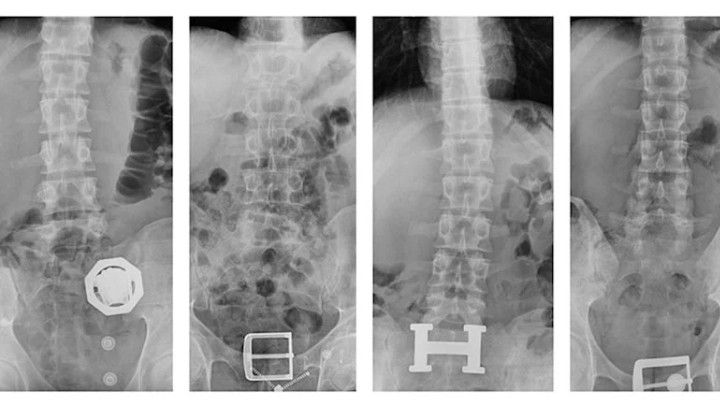

4 ?üphelinin midesinden 121 parça eroin ç?kt?!

4 ?üphelinin çekilen röntgenlerinde midelerinde 121 parça halinde 840 gram eroin tespit edildi. Uyu?turucular, yap?lan tedavinin ard?ndan ç?kar?ld?.